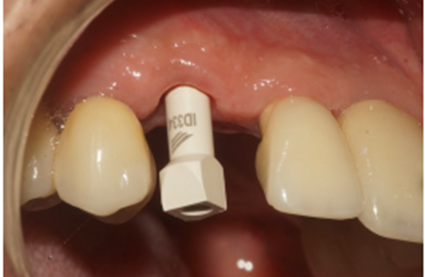

Uma vez selecionado, o pilar Ideale foi instalado e torqueado a 20 Ncm como recomendado pelo fabricante (Figura 12). Nessa mesma consulta foi colocado sobre o pilar Ideale um transferente digital referente ao mesmo e as arcadas foram escaneadas (Figuras 13, 14 e 15).

Figura 12 – Pilar Ideale de 3.3 X 4.0 X 1.5 de 17° instalado

Figura 13 – Transferente digital do pilar Ideale